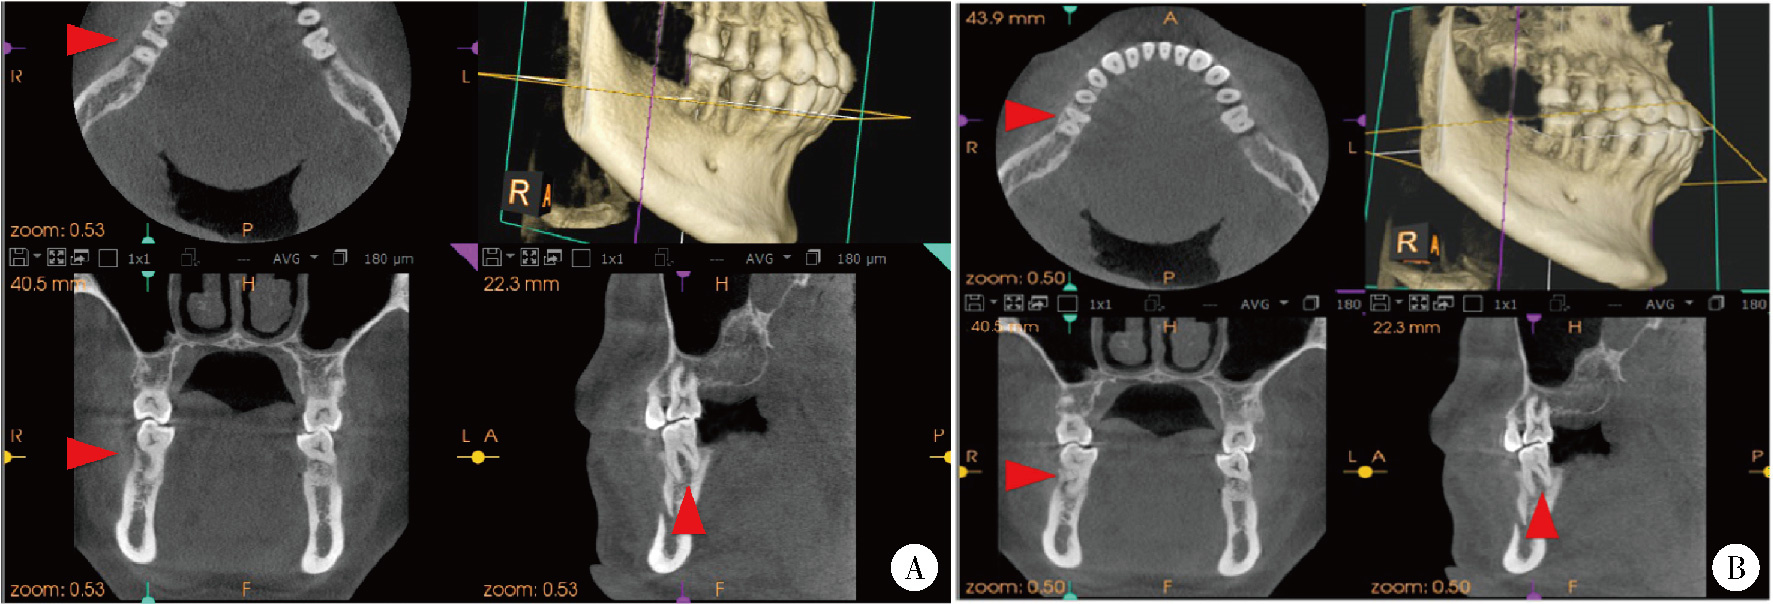

Effect of concentrated growth factors in guided tissue regeneration for the treatment of mandibular molar furcation lesions

| [14] | Fei LI,Jing QIAO,Jin-yu DUAN,Yong ZHANG,Xiu-jing WANG. Effect of concentrated growth factors combined with guided tissue regeneration in treatment of classⅡ furcation involvements of mandibular molars [J]. Journal of Peking University (Health Sciences), 2020, 52(2): 346-352. |